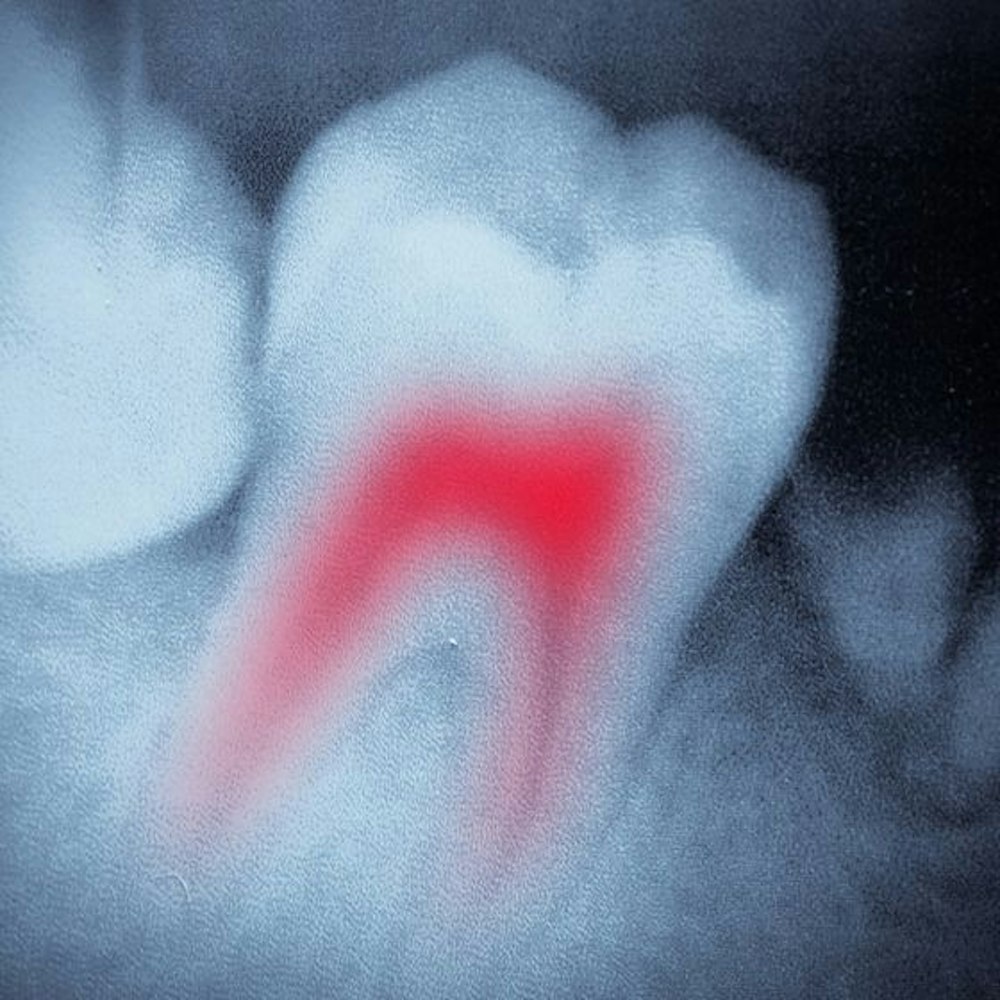

Root Canal Therapy

Traditional root canal therapy involved a lengthy procedure and a minimum of two trips to the dentist. Times have thankfully changed, and Dr. Gooch employs the use of advanced technology for quicker, easier treatment. From start to finish, including clearing infection, filling the root canal, and the placement of a permanent, custom-fitted crown, your therapy can be completed in just one visit. Our doctor offers compassionate care and is committed to keeping you comfortable while restoring your tooth to its full beauty and function.